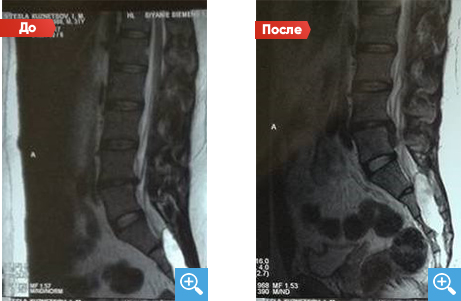

Секвестрированная грыжа

После 6 месяцев Детензор-терапии по одному сеансу 1 раз в день по 45 минут отмечается очевидный регресс секвестрированной грыжи межпозвонкового диска с 6,7 мм до 2,8 мм